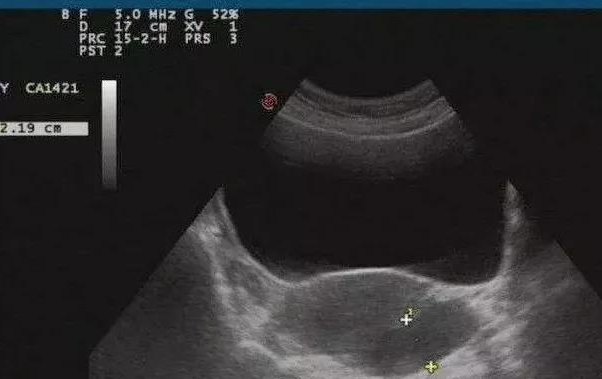

实际上,平时我们看到的B超检查提示10~30毫米的所谓盆腔积液,绝大多数是没有问题的,是生理现象,不需要治疗。

女性在站立的时候,子宫和直肠之间的盆腔间隙(叫做后陷凹或道格拉斯窝),是盆腹腔的最低点。因此盆腹腔有积液的话,都会往这里流,积在此处。躺着做的B超检查,描述的主要就是这个部位的积液。

要排出卵子,必然要破开卵泡,然后卵泡液也会跟着流出来,就积在子宫和直肠之间的后陷凹里。所以,排卵后也常常会查到盆腔积液。

排卵后或早孕期妇女,有时也会出现盆腔积液,这是生理性的,多能自行消失;有时喝过多的水或憋尿,也会产生少量盆腔积液,B超下显影一般不超过1厘米。这些情况都不用治疗。